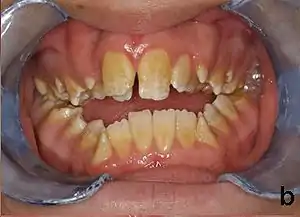

Amelogenesis imperfecta (AI) is a congenital disorder which presents with a rare abnormal formation of the enamel[1] or external layer of the crown of teeth, unrelated to any systemic or generalized conditions.[2] Enamel is composed mostly of mineral, that is formed and regulated by the proteins in it. Amelogenesis imperfecta is due to the malfunction of the proteins in the enamel (ameloblastin, enamelin, tuftelin and amelogenin) as a result of abnormal enamel formation via amelogenesis.[3]

People afflicted with amelogenesis imperfecta may have teeth with abnormal color: yellow, brown or grey; this disorder can afflict any number of teeth of both dentitions. Enamel hypoplasia manifests in a variety of ways depending on the type of AI an individual has (see below), with pitting and plane-form defects common.[4] The teeth have a higher risk for dental cavities and are hypersensitive to temperature changes as well as rapid attrition, excessive calculus deposition, and gingival hyperplasia.[5] The earliest known case of AI is in an extinct hominid species called Paranthropus robustus, with over a third of individuals displaying this condition.[6]

- Type 1 - Hypoplastic

- Enamel of abnormal thickness due to malfunction in enamel matrix formation. Enamel is very thin but hard & translucent, and may have random pits & grooves. Condition is of autosomal dominant, autosomal recessive, or x-linked pattern. Enamel differs in appearance from dentine radiographically as normal functional enamel.[20]

- Enamel has a variation in appearance, with mixed features from Type 1 and Type 2 AI. All Type 4 AI has taurodontism in common. Condition is of autosomal dominant pattern. Other common features may include an anterior open bite,[21] taurodontism, sensitivity of teeth.